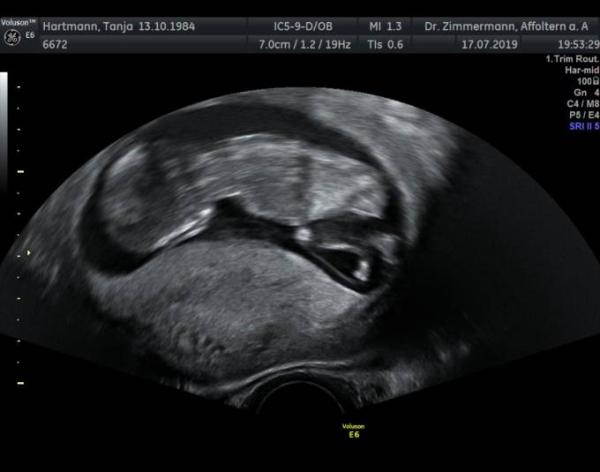

Guten Morgen ihr Lieben Gestern Abend war ich bei 12+1 beim Ersttrimesterscreening; Nackenfalte unauffällig, also alles bestens Herzchen schlägt auch ganz dolle Ob Schniepimann oder Mimmifrau konnte meine Frauenärztin noch nicht sagen. Zeigt doch mal her eure USB aus der 13.Woche

Bild zu Ersttrimesterscreening - Forum für Januar - Mamis

Ich würde tatsächlich sagen es ist ein Mädchen. Zwischen den Beinen ist so ein heller Strich. Damals erklärte mir der Arzt bei der NFM in der 13. Woche, dass wenn der strich anliegt es ein Mädchen wäre, steht er ab ein junge. Aber alles ohne Gewähr Ich bin morgen dran und schon super nervös!!!